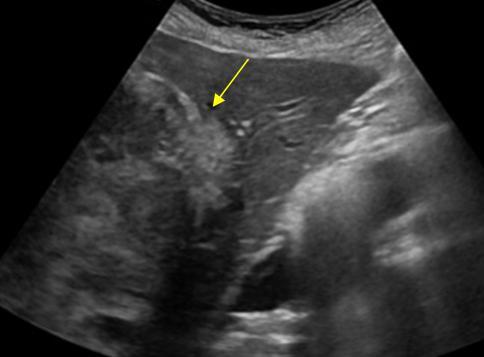

What is the sonographic appearance of Cirrhosis?

Hepatomegaly

Increased echogenicity and attenuation

Size

decrease of right lobe

Size increase of left and caudate

lobe

Nodularity

Fibrosis

Hepatospenomegaly

Ascites

Portal

hypertension

Hepatoma tumors

caudate lobe may be spared